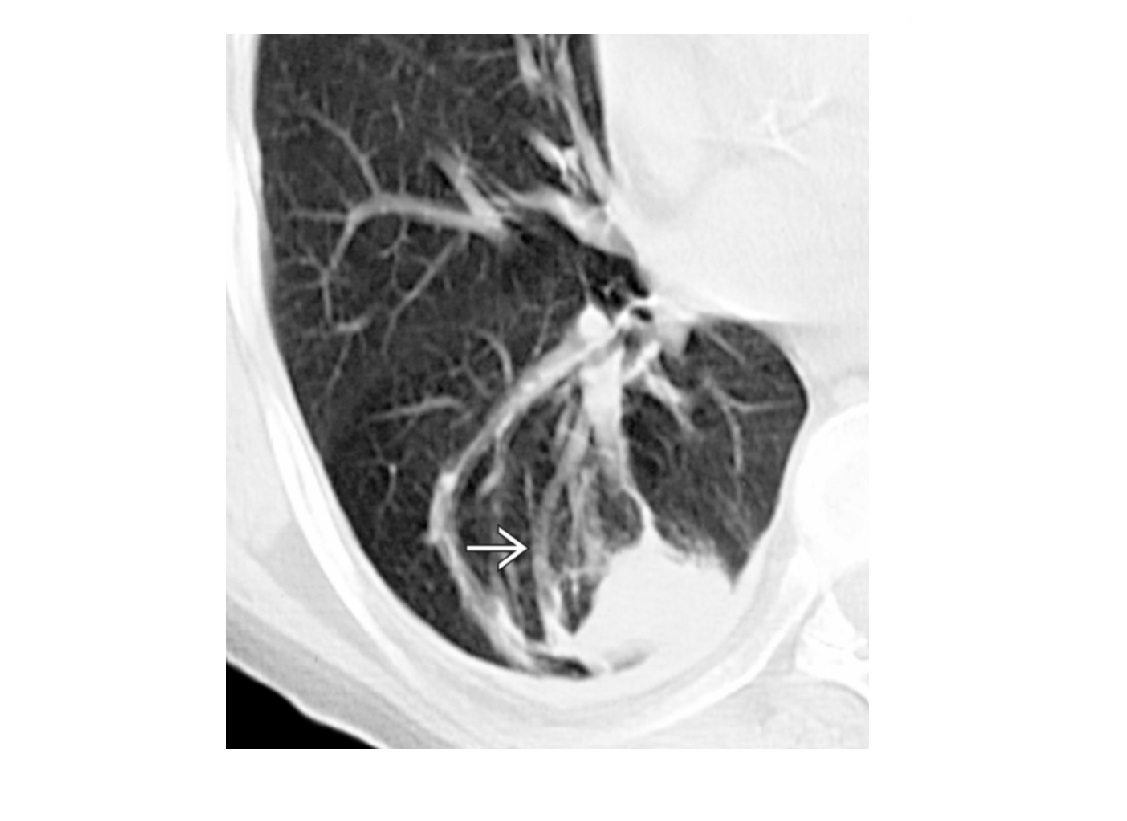

Birt-hogg-dube

Bilateral basilar predominant lentiform cysts abutting pleura, septa, and pulmonary vessels

Liver and skin lesions

Bilateral Renal oncocytomas

+ **chromophobe RCC